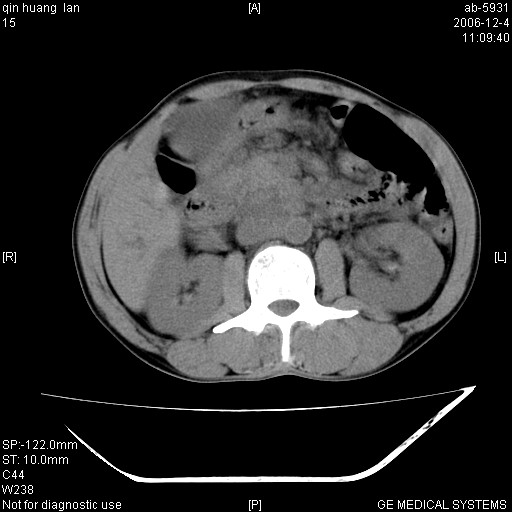

以下是引用liaoqiang在2006-12-4 15:49:00的发言:[br]1.考虑肝门区胆管细胞癌伴肝门区和腹后淋巴结肿大。2.胆总管胰腺段扩张,其下端管腔狭窄,壁厚,胰头大。考虑胆总管下段有转移灶或肿大淋巴结压迫所致。

以下是引用qiuleiyu在2006-12-4 19:07:00的发言:[br]1、无基础肝硬化表现。[br]2、左右肝内胆管明显软藤样扩张。[br]3、肝门区肿块,呈现延时花瓣样强化。而非快进快出强化。[br]4、胰头大,然密度较均,未见双管征。[br]5、后腹膜多发淋巴肿大。[br]考虑肝门部胆管ca伴胰头及后腹膜广泛淋巴转移及胆总管扩张。必要时mrcp进一步检查。

以下是引用jinguoji在2006-12-5 13:08:00的发言:[br][br]肝门区胆管细胞癌 并肝门、胰头周围、腹后淋巴结肿大转移。